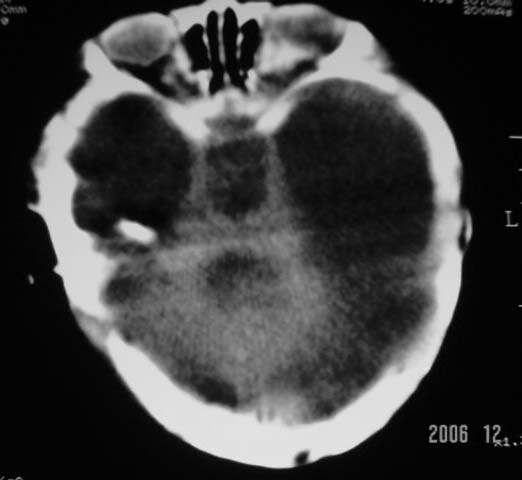

3m,出生时有新生儿吸入性肺炎、hie、化脓性脑膜炎,近一个月发现头围增大(51cm),无恶心呕吐。

3m,出生时有新生儿吸入性肺炎、hie、化脓性脑膜炎,近一个月发现头围增大(51cm),无恶心呕吐,脑室系统全程扩张,脑皮质变薄,结合病史考虑交通性脑积水

3m,出生时有新生儿吸入性肺炎、hie、化脓性脑膜炎,近一个月发现头围增大(51cm),无恶心呕吐,脑室系统全程扩张,脑皮质变薄,结合病史考虑重度交通性脑积水。